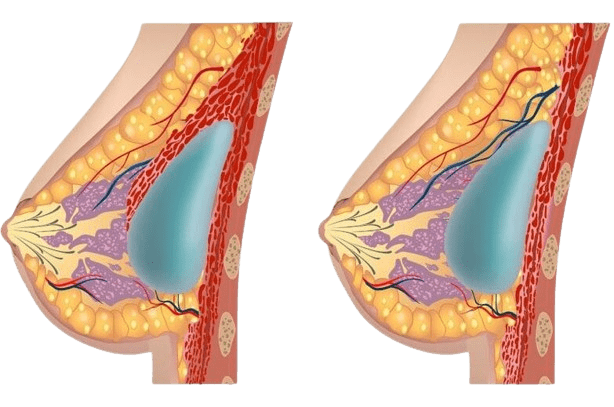

Meme büyütme operasyonu, silikon veya salin çözeltisi içeren implantlar kullanarak memelerin hacmini artırmak ve daha dolgun bir görünüm kazandırmak için yapılan bir estetik cerrahi işlemidir. İmplantlar, meme dokusunun altına veya göğüs kasının altına yerleştirilir. Bu operasyon, meme boyutundan memnun olmayan veya memelerinin şeklini iyileştirmek isteyen kadınlar için tercih edilir. Meme büyütme, kadınların vücut imajını iyileştirerek ve özgüvenlerini güçlendirerek yaşam kalitesini artırır.

Kesik yaptıktan sonra, cerrah göğüs dokunuzu göğüs duvarınızın en dış kası (pektoral kas) önünde veya arkasında bir cep oluşturacak. Cerrah, implantı bu cebe yerleştirecek ve memenizin ucunun arkasında merkezleyecektir. İmplant yerleştirildikten sonra, kesik genellikle dikişler, cilt yapıştırıcıları ve cerrahi bant ile kapatılır.